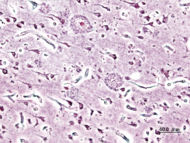

| Histopathologic image of senile plaques seen in the cerebral cortex in a patient with Alzheimer disease of presenile onset. Silver impregnation. | |

كما أن المرض يستمر بين ثمانية إلى عشر سنوات، بالرغم من أن بعض المصابين به ، قد يموتون في مرحلة مبكرة ، أو قد يعيشون لفترة 20 عاما. ويمكن للعلاج أن يساعد على إبطاء تطور الزهايمر ، ولكن لا يمكن الشفاء من المرض ، الذي سمي باسم العالم الالماني الذي اكتشفه عام 1906. ويُكتشف المرض بوجود رقع plaques ، وكتل tangles حول وداخل خلايا المخ. وتتكون الرقع من نوع من البروتين الموجود بالمخ ، بينما تتكون الكتل داخل الخلايا العصبية بفعل تشوه يصيب بروتينا آخر، وذلك بحسب ما أفادت وكالة رويترز. وبموت الخلايا العصبية ، يتقلص المخ ، ويفقد مظهره المتجعد.